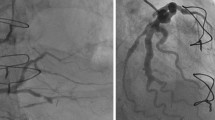

The degree of proximal stenosis in the coronary arteries was assessed by one blinded operator (SA) using quantitative coronary angiography (Horizon Cardiology version 12.2, McKesson, Israel). All TTFM measurements were performed with the VeriQC device (Medistim ASA, Oslo, Norway).

The average vessel diameter and the extent of native coronary artery vessel disease was assessed by one blinded operator (SA) using quantitative coronary angiography (QCA) (Horizon Cardiology version 12.2, McKesson, Israel).

The extent of native coronary artery vessel disease is shown in Table 3. Target vessel stenosis severity, as judged by QCA, was significant lower in the left coronary territory compared to the right coronary territory both in the overall cohort (86.1 ± 11.8% vs. 90.6 ± 9.8%, p < 0.001) and in the OPCABG cohorts (84.5 ± 13 vs. 91.7 ± 9.4%, p < 0.04) and ONCABG (87.2 ± 10.4% vs. 90.4 ± 10.1%, p = 0.002) cohorts. Non-obstructed target coronary artery diameter, average lumen diameter, and lesion length were comparable between coronary territories.